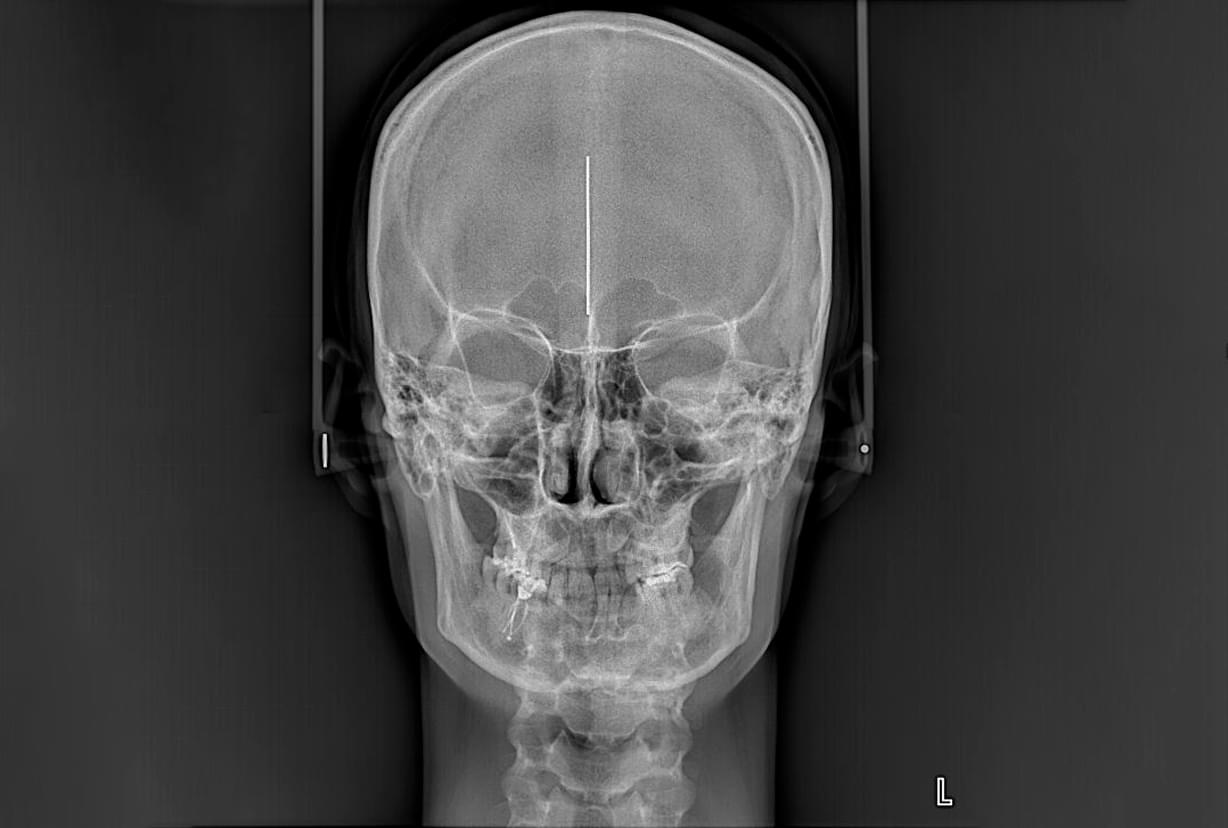

2️⃣ ТРГ у прямій проекції (Фас)

Знімок робиться спереду або ззаду.

● Що показує: Симетрію обличчя, стан носових пазух, викривлення носової перегородки.

● Для чого: Використовується при діагностиці асиметрії обличчя, перехресному прикусі або для

планування розширення щелепи.